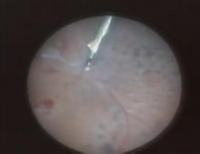

眼科内窥镜手术录像。国外医生录制,玻璃体视网膜手术为主。